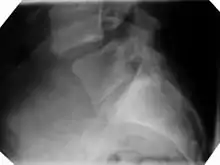

Anterolisthesis L5/S1

Anterolisthesis L5/S1. Blue arrow normal pars interarticularis. Red arrow is a break in pars interarticularis